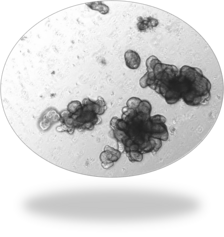

Organoïdes normaux

Organoïdes coliques : INT

Organoïdes coliques : Col

Organoïdes pancréatiques neuroendocrines: PanNET

Organoïdes murins exocrines pancréatiques normaux

Organoïdes murins pulmonaires